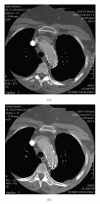

We report two cases of descending thoracic aorta floating thrombus treated with Bolton Relay thoracic free-flow stent graft. The patients had symptoms of lower limb ischemia; they underwent preoperative angiography and CTscan, then we proceeded with endovascular exclusion of the thrombus from the systemic circulation. At 12 months, the graft was still patent in both patients, without any signs of endoleak.